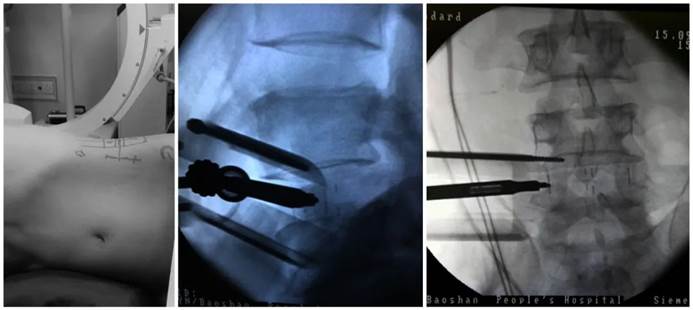

关节镜诊疗技术:被誉为“钥匙孔手术”,是骨科手术领域发展的方向。通过关节镜将纤维镜和手术器械引入关节内进行手术,以最小损伤谋取最大手术疗效,具有切口小、创伤小、疤痕小、康复快、并发症少、治愈率高、住院时间短等优点。广泛应用于膝、肩、髋关节等关节疾病的治疗,有效改善关节功能。

脊柱矫形手术

颈椎椎间盘切除椎体次全切除钢板螺钉内固定椎体融合术

微创OLIF手术